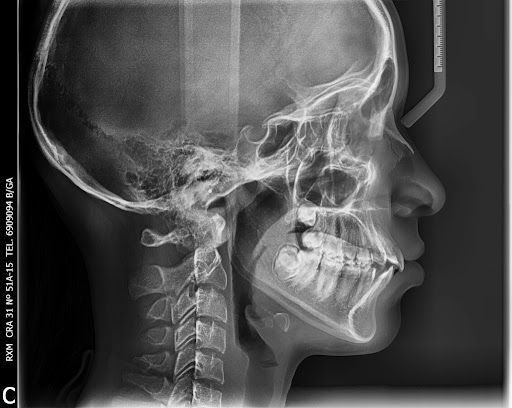

Hoy en día el uso de las radiografías se ha generalizado de tal manera que su uso se extiende a muchas áreas de salud. No obstante, las radiografías están hoy en día en el entredicho.

Y es que, las radiografías, que han supuesto un gran avance para nuestra sociedad gracias a su aplicación médica, suponen un riesgo hoy en día. Pero, ¿por qué? En el siguiente artículo te explico en qué consisten las radiografías y por qué son peligrosas.